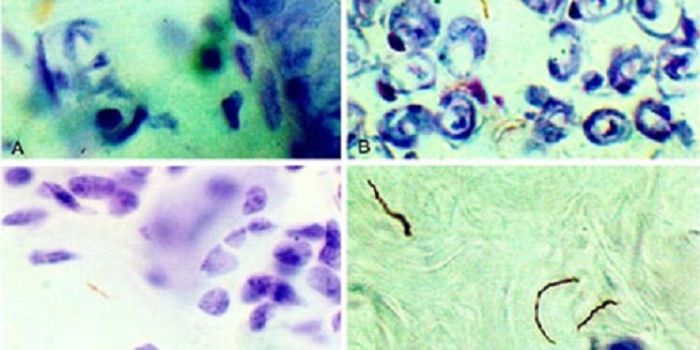

FEB 21, 2016Clinical & Molecular DXA staggering 30-50% of the world’s population is estimated to be infected with the parasite Toxoplasma gondii. Thi ...